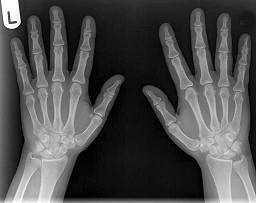

男,根据其正常手的影像图像,判断其最可能的年龄?(?)A.16岁左右B.26岁左右C.36岁左右D.76岁左右E.56岁左右

问题 男,根据其正常手的影像图像,判断其最可能的年龄?(?)

选项 A.16岁左右 B.26岁左右 C.36岁左右 D.76岁左右 E.56岁左右

答案 E